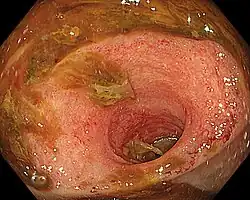

Ileítis es la inflamación del íleon, una parte del intestino delgado. La ileítis de Crohn es un tipo de enfermedad de Crohn que afecta el íleon. La ileítis es causada por la bacteria Lawsonia intracellularis.[1] La enfermedad de inflamación humana del intestino no se encuentra asociada con la infección por Lawsonia intracellularis.